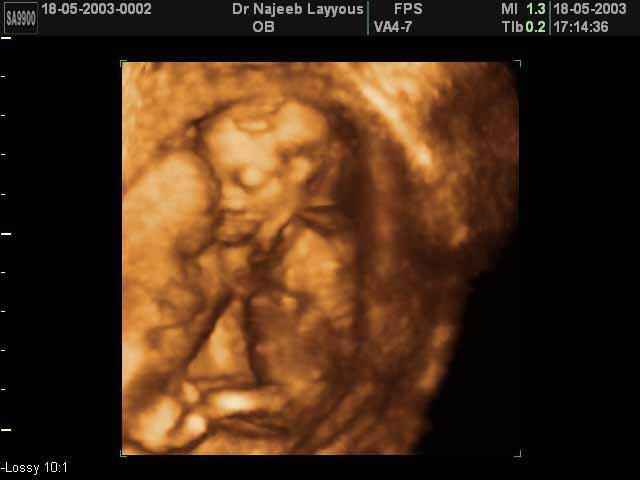

- Fetal Behavior Ultrasound Photos

3D Second Trimester Ultrasound Scan Photos-second part of pregnancy | Dr N Layyous